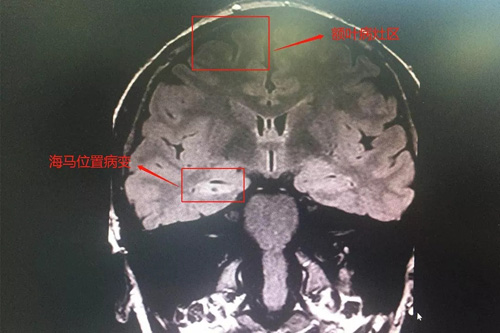

為了防止監(jiān)測(cè)過(guò)程中再次病發(fā)影響監(jiān)測(cè),醫(yī)生給我注射了鎮(zhèn)靜劑。經(jīng)過(guò)24小時(shí)不間斷觀察,終于明確了病因,崔主任介紹,我的病是一個(gè)非常典型的精神運(yùn)動(dòng)型癲癇,病灶位于右側(cè)海馬和額葉位置,有效的治療手段只有手術(shù)切除。切除了癲癇病灶,才能擺脫反復(fù)的折磨。